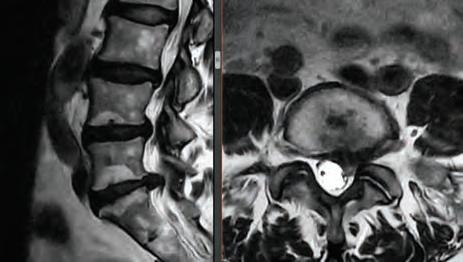

Stephen P. Courtney, MD

BOARD-CERTIFIED, FELLOWSHIP-TRAINED ORTHOPEDIC SPINE SURGEON PRACTICING FOR 26 YEARS.

For board-certifid, fellowship trained orthopedic spine surgeon

Dr. Stephen P. Courtney, patients come fist. It’s an ethos that developed early on in his life and one that has helped guide him in his journey to earn a distinguished reputation among his professional colleagues, medical peers and, most importantly, his patients.

Dr. Courtney’s residency at Texas A&M University Medical Center and further specialty training through a fellowship at Florida Neck & Back Institute in Gainesville, Florida, additionally cemented his strong medical foundation. From there, he continued to gain more knowledge and insight on how to help his patients with useful tools, while recognizing there was room for much improvement in the tools at hand.

Ths realization inspired Dr. Courtney to design, develop, biomechanically test, complete FDA testing and oversee quality control and

validation on a host of tools he created. To date, Dr. Courtney has developed nine spinal product lines and obtained nine patents and 14 trademarks on spine related products.

When he’s not traveling the country training other physicians on how to utilize his products, Dr. Courtney dedicates himself to the patients of his own medical practice, Advanced Spine Center.

Led by Dr. Courtney, the skilled team at Advanced Spine Center cares for patients with neck and back pain using a wide array of the most state-of-the-art tools and techniques—from conservative physical therapy and injection therapy—to advanced pain management, as well as surgical intervention. We employ the latest in minimally invasive spine surgeries, in addition to cutting-edge replacement technology. Incorporating both high tech and high touch, we get our valued patients back to their lives so they can enjoy all the activities they love.

SURGERY: L5/S1 360° LUMBAR FUSION

SURGERY: LEFT L5/S1 MICRODISCECTOMY

SURGERY: C4/C5, C5/C6, C6/C7 ACF (ANTERIOR CERVICAL FUSION)

SURGERY: L4/5, L5/S1 360° LUMBAR FUSION